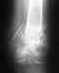

10.01.10 муж сломал ногу. Наложили гипс.диагноз:перелом лодыжки без видимого смещения.Врач не хочет делать контрольный снимок, говорит ходить с гипсом месяц потом придете. Скажите, на самом деле нет смысла делать контрольные снимки сейчас или лучше сделать?рениген-снимок прилагается.

• Кликните для загрузки файла Scan0002.jpg